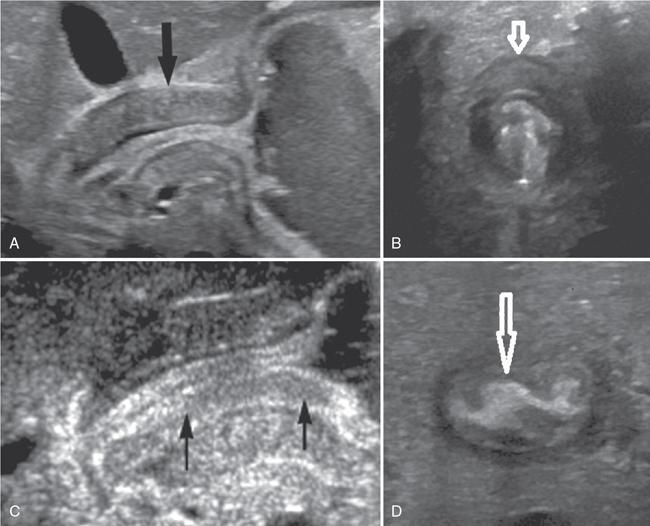

Fig. 7.4.1.1Midline epigastric scan showing symmetrically thickened hypoechoic muscle of the pylorus with central echogenic mucosa.

Ultrasonography (USG) of abdomen: Usually performed in the right lateral decubitus position to allow fluid to distend the antral region.

USG reveals a target sign seen as a thickened hypoechoic muscle mass of the hypertrophied pylorus surrounding the central echogenic thin mucosal line.

USG: This is the preferred imaging modality as it is noninvasive and does not pose any radiation hazard. USG is performed with a 6–10 MHz linear probe. Fluid distention of the stomach can aid in visualization of the pylorus. A sausage-shaped mass with a total thickness of more than 14 mm and length in excess of 16 mm with each wall measuring at least 4 mm is indicative of congenital hypertrophic pyloric stenosis.